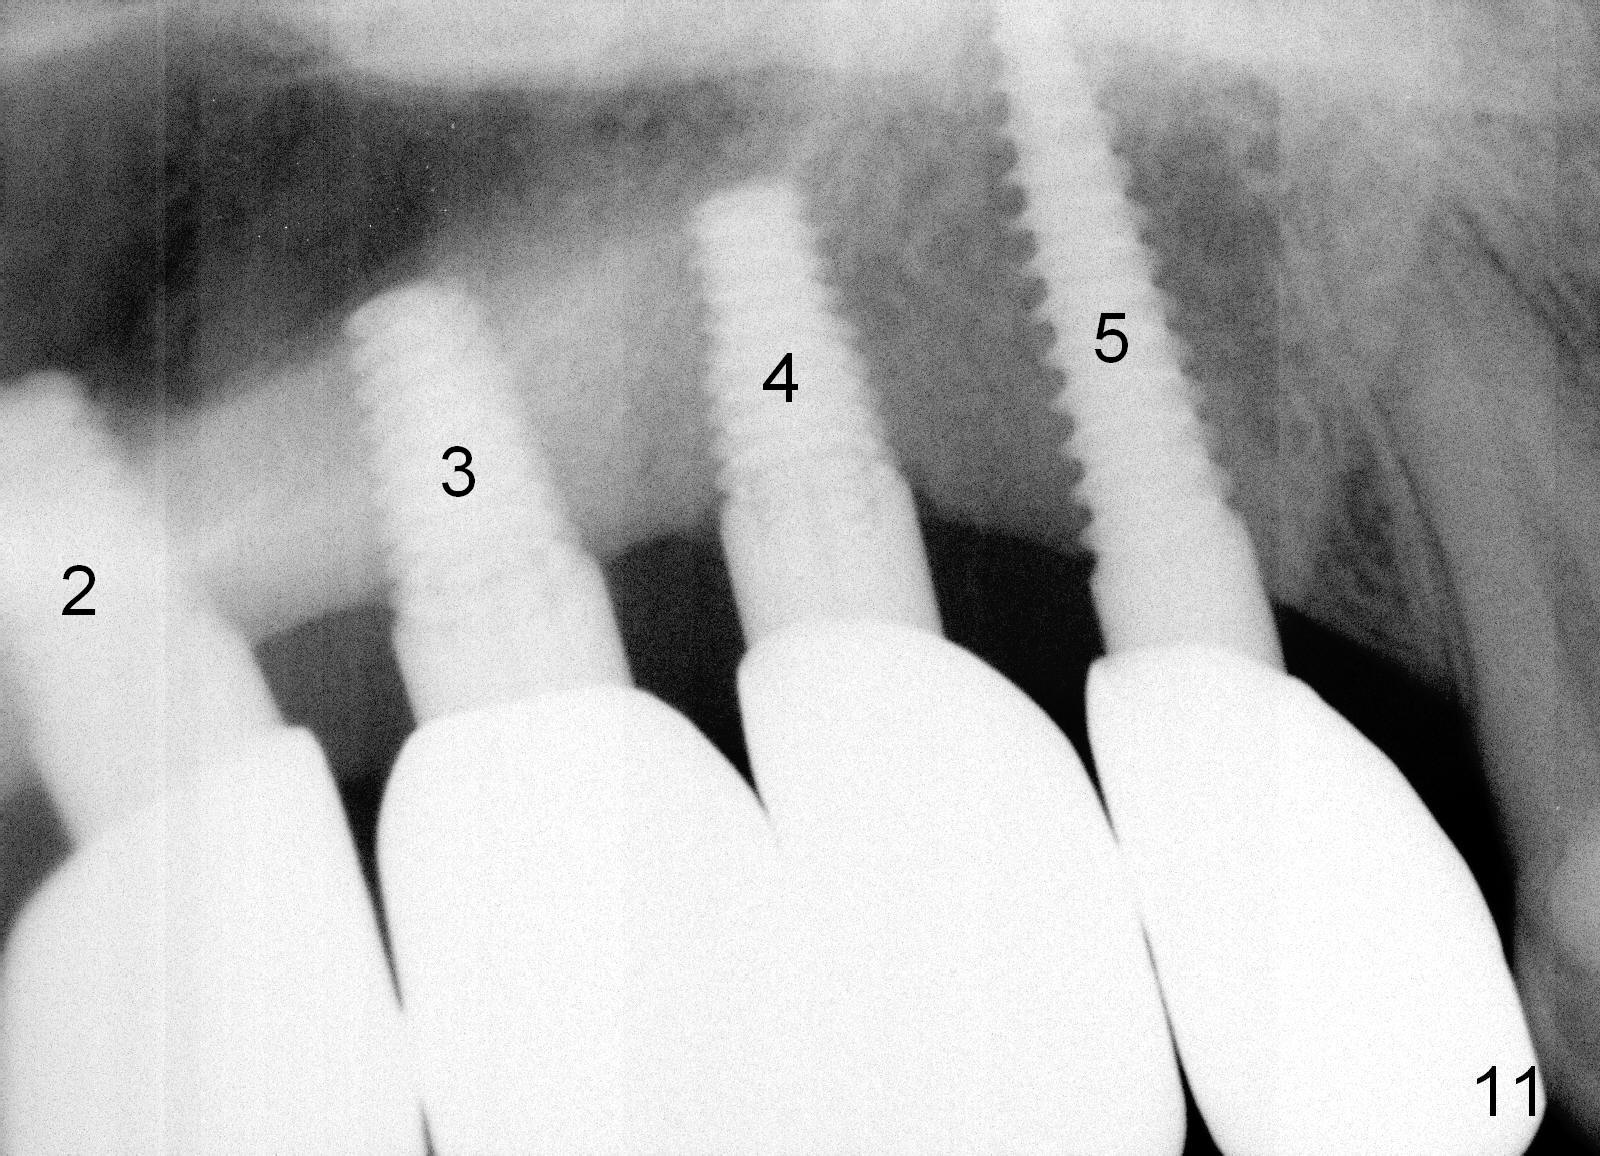

There is no apparent bone loss around the implants 13 months post immediate provisional, 5 months post cementation of non-splinted permanent restoration (Fig.10,11).